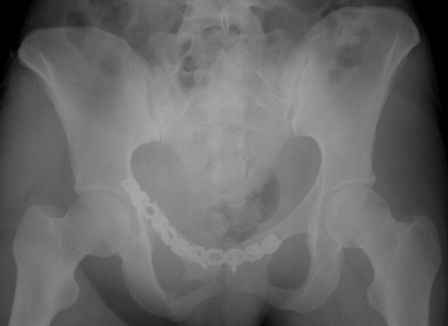

Re: перелом таза

Серия до- и послеоперационных снимков этой пациентки. Хотя бы post factum обсудить. Не знаю, что можно сделать с задними отделами стержневым аппаратом, но три крепких парня открытым путем с помощью "волшебных" слов еле-еле смогли отрепонировать - сзади все было очень ригидно!